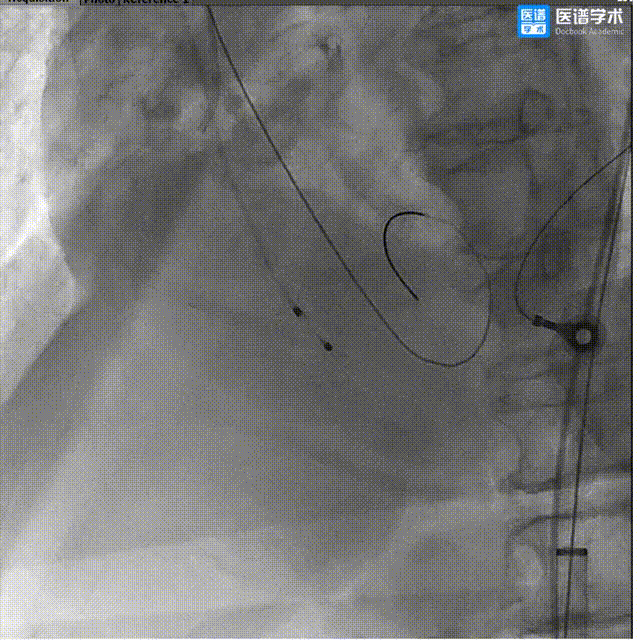

6、术中讨论决定行右冠保护措施,经右桡动脉送入6F JR3.5指引导管,行右侧冠脉造影,示患者右侧冠状动脉近段狭窄;

7、经6F JR3.5指引导管,送入3.5×28mm支架至RCA近段,预备行烟囱支架术;